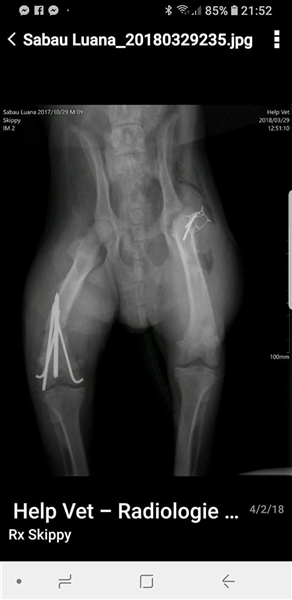

Skipper wurde im Oktober 2017 geboren, hat eine Schulterhöhe von knapp 50 cm und ist kastriert. Der Rüde wurde verletzt im Straßengraben gefunden, beide Hinterbeine waren gebrochen, doch er konnte erfolgreich operiert werden. Er ist inzwischen wieder flott auf seinen vier Beinen unterwegs, auch wenn sein Bewegungsablauf nicht ganz rund ist, so schränkt ihn seine minimale Behinderung nicht ein, fällt auch kaum auf und er ist auf seinen vier Beinen flott unterwegs. Der hübsche Rüde wird vielleicht nicht der ideale Begleiter für längere Joggingrunden oder Radtouren sein, aber nicht jeder Mensch ist ein Sportfreak und Skipper ist auf keinen Fall ein Couchpotato. Skipper lebt seit Juli bei einer Pflegefamilie in Dortmund zusammen mit anderen Hunden und kann dort gerne kennengelernt werden.